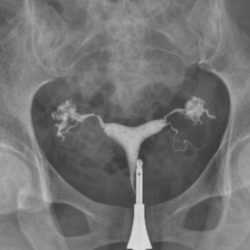

During tubal ligation, the fallopian tubes can be tied, cut, or closed using special techniques. Which technique is used may vary depending on the patient’s condition and the surgeon’s preference. The procedure usually takes a short time, and most patients are discharged the same day or the following day.